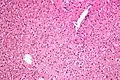

- Micrograph showing ground glass hepatocytes. H&E stain.

In liver pathology, a ground glass hepatocyte, abbreviated GGH, is a liver parenchymal cell with a flat hazy and uniformly dull appearing cytoplasm on light microscopy. The cytoplasm's granular homogeneous eosinophilic staining is caused by the presence of HBsAg.

The appearance is classically associated with abundant hepatitis B antigen in the endoplasmic reticulum, but may also be drug-induced.[1][2] In the context of hepatitis B, GGHs are only seen in chronic infections, i.e. they are not seen in acute hepatitis B.